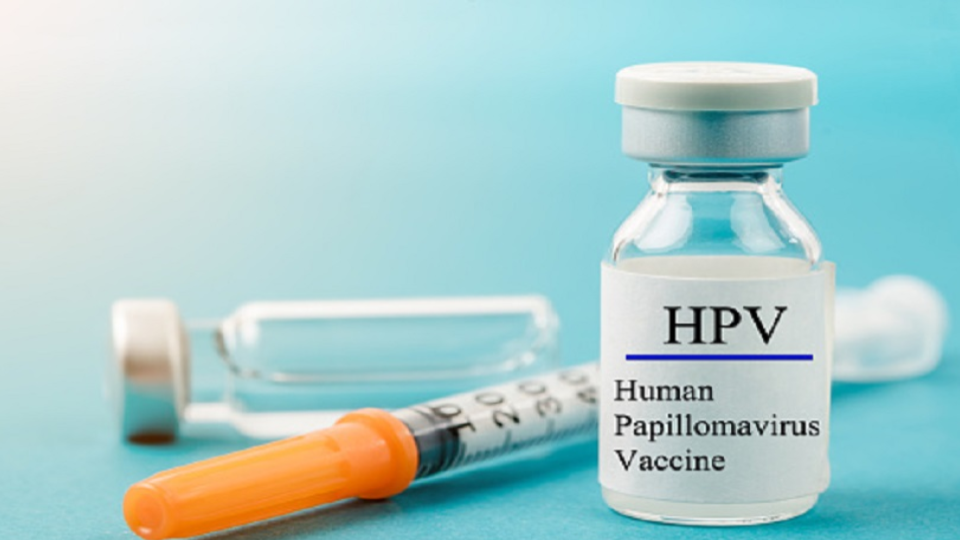

Sikkim has initiated a state-wide vaccination campaign aimed at protecting girls from Human Papillomavirus (HPV), a virus linked to cervical cancer, which is prevalent among women...

Prime Minister Narendra Modi officially launched the nationwide Human Papillomavirus (HPV) Vaccination Programme today in Ajmer, Rajasthan. This initiative aims to provide vaccinations to girls aged...

Chief Minister N. Chandrababu Naidu is set to launch a significant Human Papillomavirus (HPV) vaccination programme in the Vizianagaram district today, March 15, 2024. This initiative...